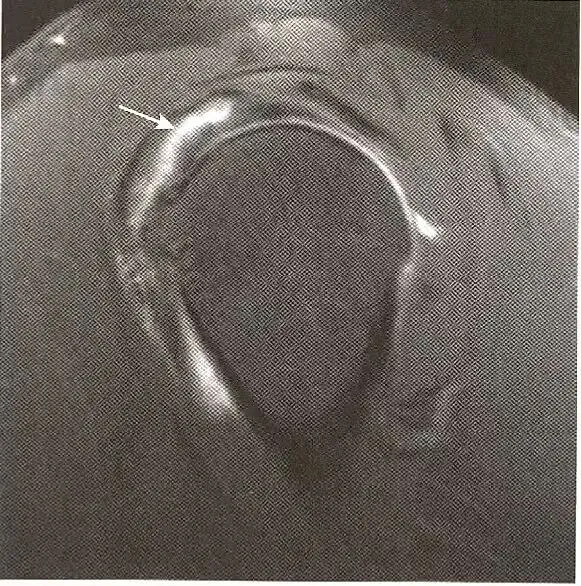

肌腱部分撕裂—层状撕裂:  冈上肌肌腱水平样分裂。